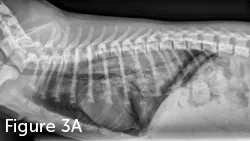

Diagnosis of NCPE is often based on history, examination, and radiographic imaging. Classic radiographic findings include increased interstitial or alveolar opacity, notably in the caudodorsal lung fields (Figure 3). This contrasts with radiographic findings in patients with cardiogenic pulmonary edema, notably perihilar edema. However, other forms of respiratory disease should be investigated, including cardiogenic pulmonary edema, pneumonia, and hemorrhage from trauma or coagulation abnormalities. Echocardiography can exclude cardiogenic edema and left-sided heart failure. A coagulation profile should be performed and pneumonia ruled out based on history, physical examination findings (eg, nonfebrile), and CBC results.

FIGURE 3

Lateral (A) and VD (B) thoracic radiographic views of a dog with NCPE. Note the focal interstitial to alveolar pattern present in the 3 caudodorsal lung fields.